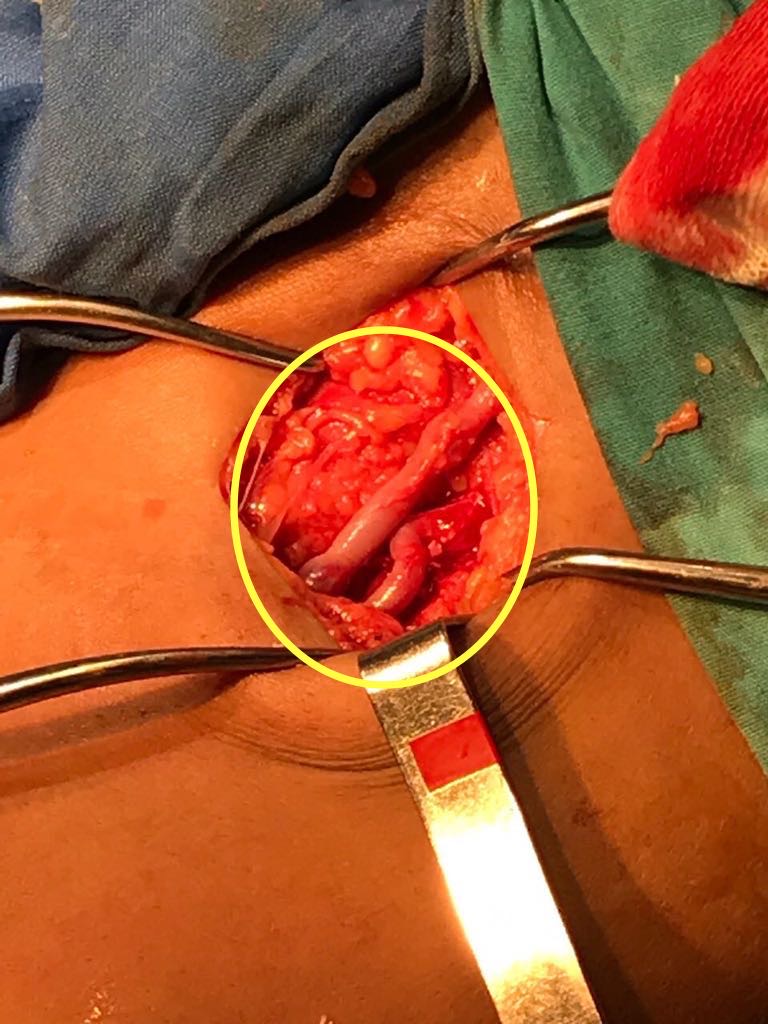

Ante el aumento de la población en diálisis y el tiempo en que los pacientes permanecen bajo este tratamiento aparece otro problema, quizás más importante, que es el agotamiento los de accesos vasculares convencionales y habituales en miembros superiores. Debido a esto se han ido desarrollando alternativas en la confección de accesos en miembros inferiores, como la fístula safeno-femoral (Imagen 1 y 2),(7) safeno-tibial(8) y también la utilización de vena femoral superficial transpuesta al muslo o como injerto autólogo donado al miembro superior.(9-10) Ello representa una alternativa a la confección de accesos protésicos y a la utilización de catéteres permanentes, ya que los accesos nativos poseen mayor índice de permeabilidad.(4, 8)

Esto lleva a la desafiante necesidad de rescatar este tipo de fístulas, ante la aparición de disfunciones, con métodos quirúrgicos convencionales y endovasculares. Se presenta un caso clínico de una joven de 27 años de edad, en HD trisemanal desde hace diez años, debido a nefropatía lúpica, diagnosticada cuatro años antes de su ingreso a diálisis. La misma presentaba agotamiento de accesos vasculares en ambos miembros superiores por múltiples FAV nativas y protésicas con abordaje auxiliar bilateral asociada a angioplastia axilar izquierda. Ingresa con FAV safeno-femoral en loop izquierdo disfuncionante, de siete meses de evolución con hipoflujo y kTv inadecuado. Con el examen físico se constató escaso frémito y latido.

Se realizó abordaje del tercio medio de la fístula, con anestesia local y sedación anestésica, bajo control radioscópico con Arco en C Philips Pulsera®. Se realizó punción retrógrada de vena safena, por visión directa con introductor de 5 Fr, se progresó con cuerda hidrofílica de 0.035x260 atravesando lesión obstructiva hacia la arteria femoral común (Imagen 3).